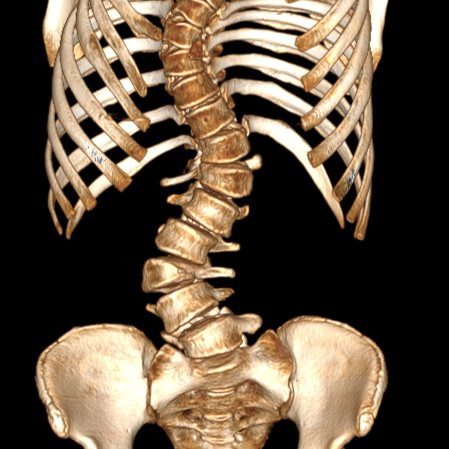

17-летняя пациентка поступила в больницу с S-образным сколиозом 3-4 степени. Это тяжелая форма искривления позвоночника — для неё характерна выраженная деформация, которая вызывает ярко выраженный болевой синдром и существенно ограничивает подвижность. Кроме того, такая патология несет серьезную угрозу развития осложнений со стороны внутренних органов и может спровоцировать возникновение сопутствующих заболеваний. Консервативные методы лечения в данном случае были бы малоэффективны и специалисты приняли решение провести сложную, трудоемкую операцию по исправлению деформации и фиксации нормального положения позвоночника.

«Сколиоз – это ортопедическое заболевание, которое характеризуется сложной деформацией одновременно в нескольких плоскостях позвоночного столба и грудной клетки. Сопровождается нарушением функции органов и систем организма, является причиной тяжелых физических и психологических трудностей у детей. Обычно бывает достаточно комплексного консервативного лечения: это лечебная гимнастика, массаж, корсеты и другие методы. Редко, при работе с особенно тяжелыми случаями, требуется хирургическое вмешательство. В нашей больнице такую операцию проводили впервые, она заняла около десяти часов, потребовалась слаженная работа высококвалифицированных специалистов разного профиля – анестезиологов, нейрофизиологов, трансфузиологов, нейрохирургов, травматологов-ортопедов. В ходе хирургического вмешательства применили современный метод коррекции сколиотической деформации. Вдоль позвоночника на разных уровнях установили транспедикулярные винты. Затем на них слева и справа наложили специальные стержни, предварительно изогнутые с учетом коррекции деформации позвоночника и физиологических изгибов, они были закреплены гайками. Это конструкция позволила зафиксировать нормальное положение позвоночника и исправить искривление», — рассказал Исмаил Османов.